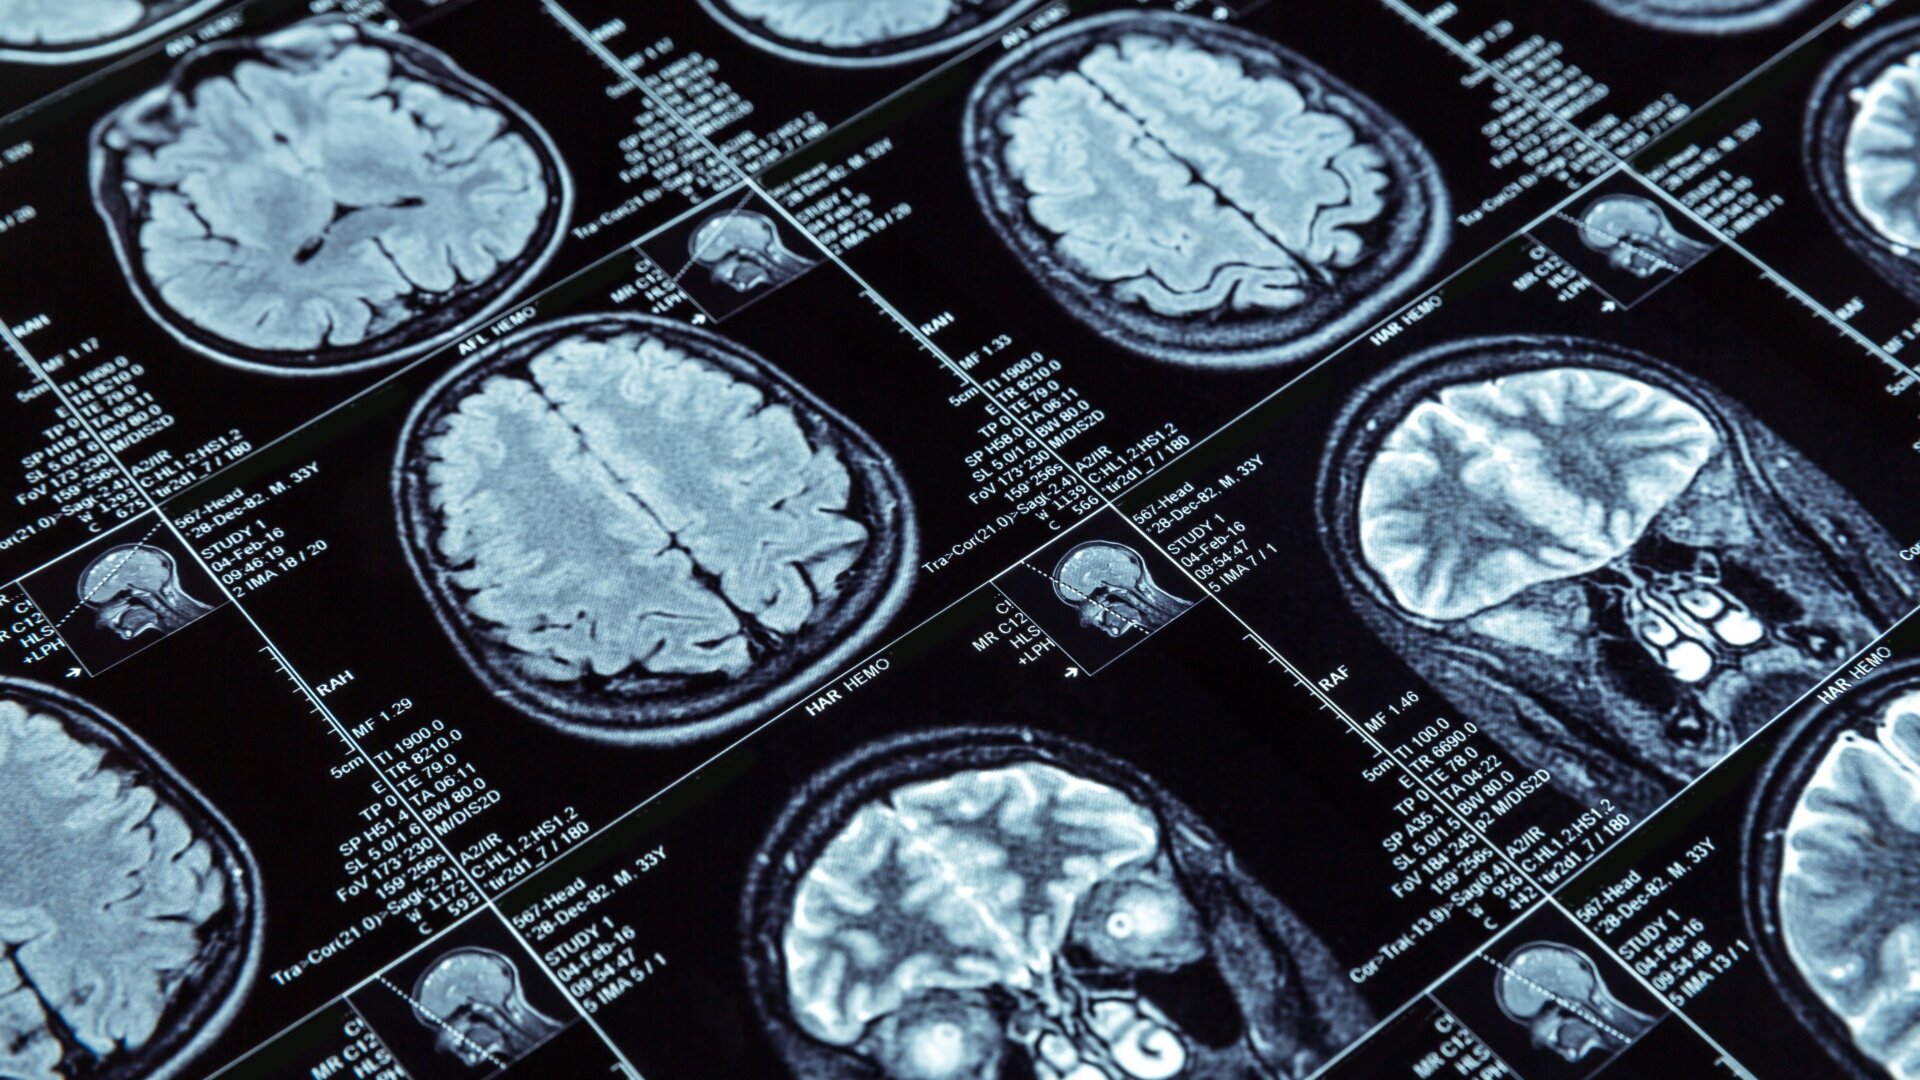

Cette nouvelle recherche, publiéMercredi, dans Nature Communications, pourrait être l’une des analyses les plus complètes des patients atteints d’EM/SFC à ce jour. Elle a été menée par des scientifiques de les Instituts nationaux de la Santé, dans le cadre d’une initiative d’étude de la maladie qui a commencé en 2016. Les chercheurs ont recruté des volontaires soupçonnés de avoir une EM/SFC et finalement sélectionner 17 patients pour soumettre une série d’examens médicaux, tels que un prélèvement de liquide rachidien, des scintigraphies cérébrales , des biopsies cutanées et des analyses de sang. Ces patients ont ensuite été comparés à des témoins sains.

Par rapport à la base des contrôles, les patients atteints d’EM/SFC présentaient des différences biologiques claires, ont découvert les chercheurs. Les patients étaient plus susceptibles d’avoir une partie inférieure du cerveau. par exemple, dans la région de la jonction temporo-pariétale du cerveau. Ils ont également tendance à avoir des niveaux plus faibles de neurotransmetteurs appelés catécholamines. ainsi que des niveaux altérés de certaines cellules immunitaires et des signes possibles d’épuisement immunitaire.